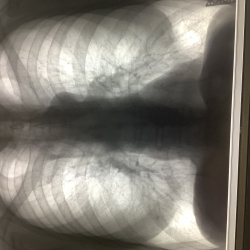

Флг, 15 лет, справа в кардиодиафрагмальном углу суммация рёбра и НПВ? Или всё же липома?